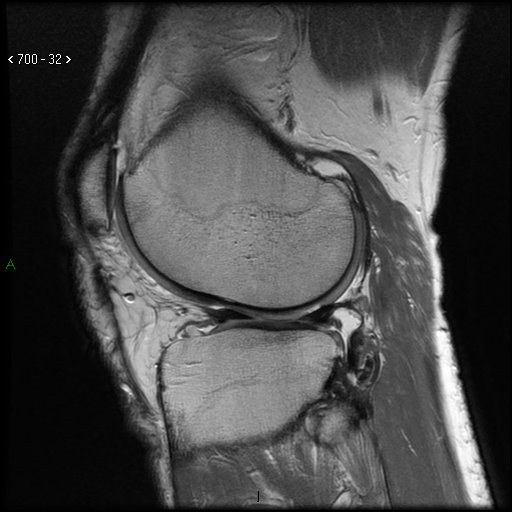

An example of an MRI examination performed at the Carolina Medical Center in Warsaw and another medical facility:

Images of the knee joint – damage to the meniscus and cartilage (MRI)

Fig. 1 – examination performed at the Carolina Medical Center